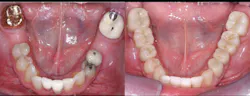

• Use resin-modified glass ionomer (RMGI) cement for zirconia restorations when the tooth preparations have near-optimum characteristics. See Figures 4 through 6 for examples of these characteristics. Most clinicians and researchers would agree that the tooth preparation should be at least 4 mm in height from the gingival margin to the occlusal table, and that the lack of parallelism of the preparation walls should be up to, but not more than, 20 degrees from the long axis of the tooth being prepared.

Figures 4-6: Images showing an adequate impression, the die of an adequate tooth preparation, and the resultant full-zirconia crowns.

Figure 4

Figure 5